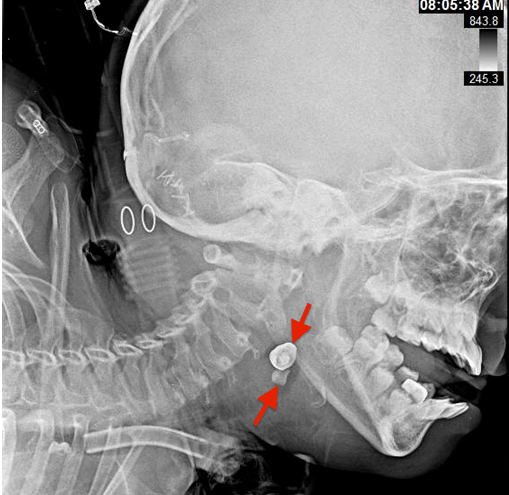

Figure 4: An eight-year-old boy with two radiopaque densities incidentally found on modified barium swallow study. Findings: Two radiopaque objects (red arrows) at the level of the hypopharynx near the cervical esophagus. Technique: Lateral skull plain radiograph performed eight months prior to discovery of foreign bodies on modified barium swallow study.

An eight-year-old neurologically devastated boy residing in a specialized nursing home for medically frail children was brought into the emergency department for evaluation of two foreign bodies found incidentally on modified barium swallow study (MBSS). The patient has a history of posterior fossa arteriovenous malformation (AVM) rupture causing large left sided cerebellar hemorrhage that left the patient gastrostomy tube, tracheostomy, and ventilator dependent. Since the AVM rupture, the patient experienced continuous bruxism and tongue biting that required him to wear a mouth guard. The swallow study was performed for evaluation of swallowing prior to advancing his oral intake. Oddly, the patient had been completely asymptomatic with no changes in his ventilator requirements despite the impaction of these foreign bodies. He had been tolerating his gastrostomy tube feeds and did not seem like he was in pain. X-ray of the neck soft tissue lateral view (Figure 1) and anteroposterior view (Figure 2) showed two radiopaque densities ~5–10 mm each, which have the appearance of teeth within the hypopharynx/vallecula at the level of C3 and C4. Consultation to otorhinolaryngology team was initiated. Patient was scheduled for removal in the operating room under general endotracheal anesthesia. The foreign objects were removed under direct visualization with direct laryngoscopy and forceps. The remainder of the laryngoscopic examination was normal. Pathology was consistent with two irregularly shaped shiny golden metallic dental crowns measuring 1.0x0.6x0.6 cm and 1.1x0.8x0.6 cm. A photograph of the dental crowns was taken (Figure 3). It is unclear when our patient lost both his crowns and how long they were in his hypopharynx. However, on chart review, a lateral X-ray of the skull (Figure 4) performed eight months prior to discovery of the foreign bodies on the MBSS showed the two radiographic densities in the same place. This indicates that these dental crowns may have been impacted in the patient's hypopharynx for over eight months. The identification of these two radiographic densities was missed on the initial skull X-ray read. Additionally, a dental consult and examination was performed on the same day as the skull X-ray, which failed to detect the missing dental crowns but showed that his mouth-guard was loose and that teeth 7–10 and 23–26 were mobile/loose.

If foreign body ingestion is suspected, plain radiography should be the initial method of investigation. Plain radiographs can confirm the size, location, and shape of ingested foreign objects and help rule out aspiration. They are also helpful in excluding some complications including pneumomediastinum (in case of viscus perforation) or crepitus (if there is an infection). Since, the skull X-ray was ordered to evaluate for a left-sided head lump, it is possible that most of the reading radiologist's attention was focused on ruling out a fracture. For this reason, radiologists should keep an open mind about the differential diagnosis and remain open to the possibility of unusual findings, as they are least likely to be biased by patient's clinical presentation. We also suggest that performing serial plain radiographic evaluation of neck, chest and abdomen when missing dental prosthetics is suspected in individuals at high risk for asymptomatic accidental ingestion (such as our patient). Initial plain radiographs will confirm if accidental ingestion of radiopaque objects has occurred. Subsequent serial plain radiographs will ensure timely passage of these foreign objects or dictate appropriate further management to prevent further complications associated with foreign object impaction in the aero-gastrointestinal tract.